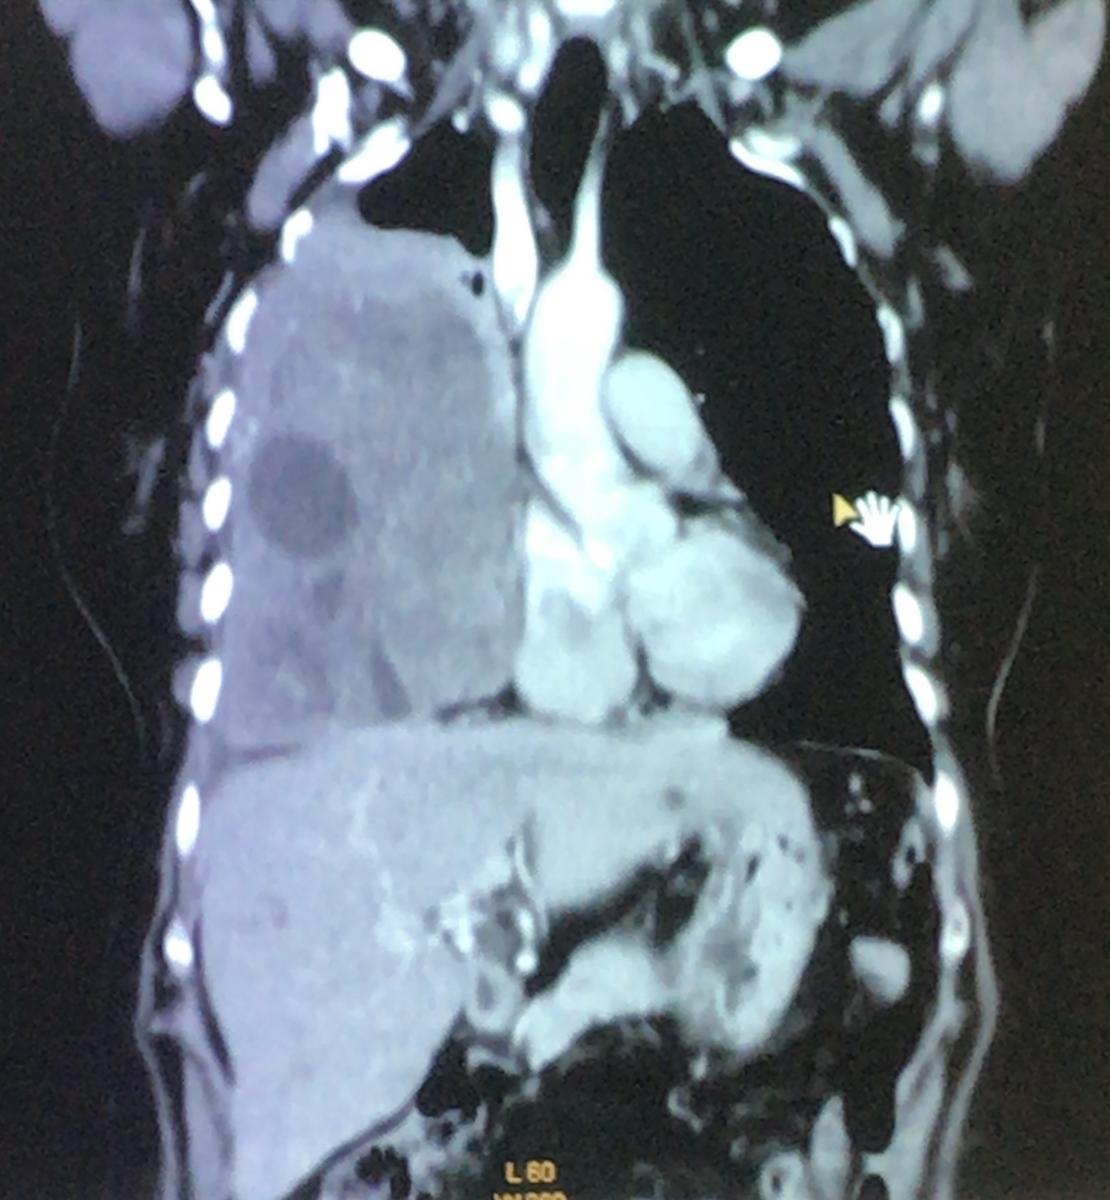

Figure 1. Coronal section of computed tomography, where heterogeneous lesion with cystic area is observed, which displaces the mediastinum, collapses the lung, and flattens the diaphragm.

The physical examination showed the abolition of vesicular murmur in the lower, middle, and part of the upper pulmonary field. She brought spirometry with severe restrictive pattern. Thoracic computed tomography (CT) was performed, where a heterogeneous voluminous mass was observed, with cystic areas, in the right lung, 126 x 166 mm in size, in intimate contact with the thoracic wall, diaphragm, and mediastinal structures (figure 1).